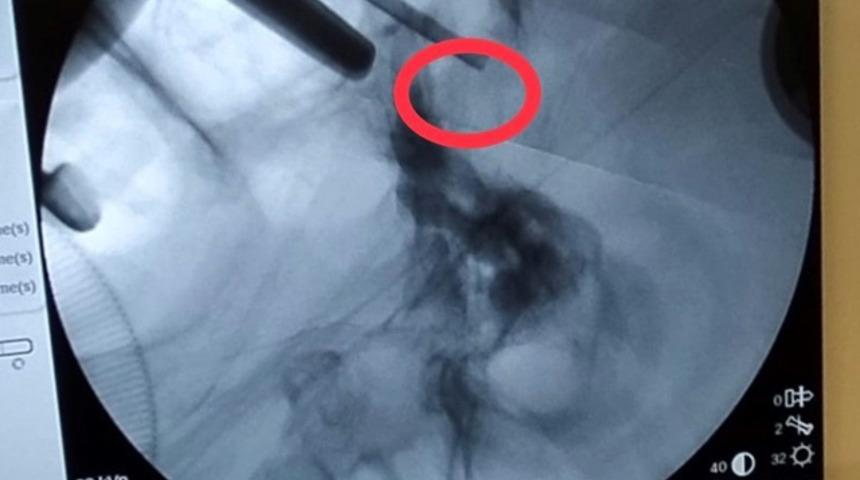

Görme kaybıyla kentteki özel bir hastaneye başvuran ve ismi açıklanmayan Uşaklı 72 yaşındaki hastaya yapılan tahlil ve tetkikler sonucunda hipofiz bezine yerleşmiş ve kafa tabanındaki sinirlere bası yapan bir tümörün varlığı tespit edildi. Beyin ve Sinir Cerrahi Uzmanı Op. Dr. Celal Özbek Çakır tarafından operasyon yapılmasına karar verildi. Ameliyata alınan hastanın burun deliklerinden girilerek beynindeki tümör alındı.

Operasyon sonrası açıklamalarda bulunan Çakır, transsfenoidal cerrahinin burun boşluğundan girilip hipofiz tabanına ve oradan hipofize ulaşılıp yapılan cerrahi olduğunu söyledi. Çakır, "Hastamız da 72 yaşında, ani gelişen göz kapağında düşme, görme kaybı ve şiddetli baş ağrısı ile bize geldi. Hastanın tetkiklerinde sella dediğimiz kafa tabanında hipofiz bezinin yerleştiği boşlukta büyük bir kitle ve buna bağlı bu bölgedeki kranial sinirlerin bası altında kaldığını görerek cerrahi kararı aldık. Hastaya transsfenoidal girişimle tümörü tamamen boşalttık ve problemsiz olarak servise aldık" dedi.